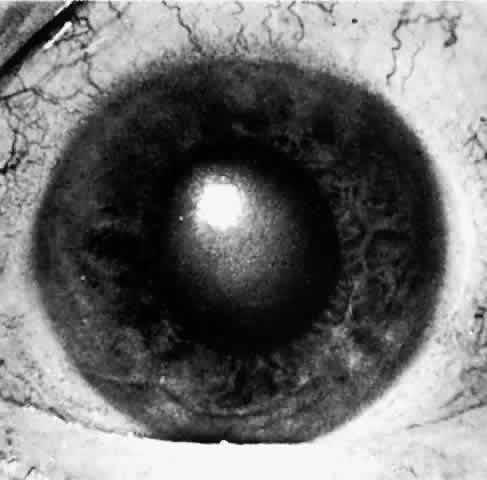

On early examination, the cardinal sign of primary acute angle-closure glaucoma is present: a fixed mid-dilated pupil. There is profound reduction in central visual acuity. Photophobia and conjunctival hyperemia are striking external findings (Fig. 6). Intraocular pressure usually exceeds 40 mmHg and may be as high as 70 or 80 mmHg during the attack. On biomicroscopy, perilimbal hyperemia with a ciliary flush is accompanied by peripheral conjunctival and episcleral congestion. The peripheral iris bulges anteriorly and comes in close contact with the peripheral corneal endothelium for 360 degrees. Early microcystic epithelial corneal edema evolves to stromal edema. The anterior chamber appears shallow but formed centrally with cells, pigment and aqueous flare. Sustained high intraocular pressure affects the iris sphincter muscle, as well as its blood supply.33 Ischemia of sectors of the iris develop, probably due to compression of nutrient radial iris vessels causing infarction of the compromised iris and possibly also the ciliary body. This results in the release of debris and proteins, causing an aseptic anterior uveitis.

Fig. 6. A most reliable sign in angle-closure glaucoma is the unreactive pupil in the mid-dilation. Conjunctival and ciliary vascular engorgement, as well as epithelial corneal edema, is present. In this eye, no atrophy of the iris is visible, but the iris sphincter is unreactive, presumably as a result of ischemia caused by the elevated intraocular pressure. If high pressure is relieved before permanent atrophy of the iris occurs, the pupil will again become reactive. (Courtesy of Ayerst Laboratories and Dr. H. Saul Sugar)